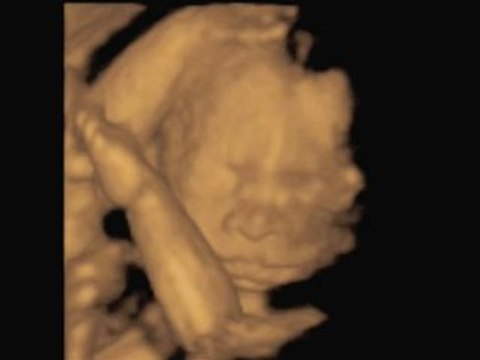

3D Ultrasound

Uploaded: February 24, 2015 Views: 1

3D Ultrasound (espa

Uploaded: February 24, 2015 Views: 27